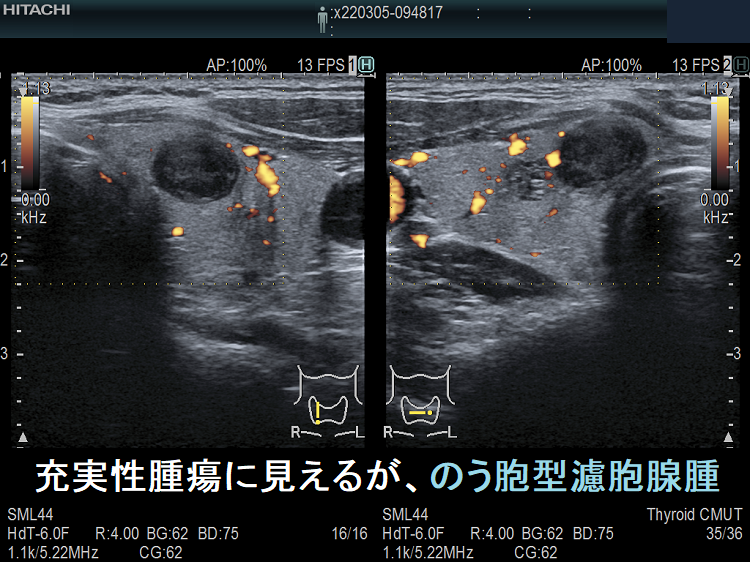

ケース⑤ 甲状腺充実性腫瘍でなく甲状腺のう胞腺腫(甲状腺嚢胞腺腫)

充実性腫瘍に見えるが、のう胞腺腫

通常Bモードでは、充実性腫瘍に見える。

高感度パワードプラーで低流速の細い血管が検出されず、甲状腺のう胞腺腫(甲状腺嚢胞腺腫)(内部の不均質な実質様エコーは粘稠なコロイド物質)

ケース⑥ 甲状腺充実性腫瘍でなく甲状腺のう胞腺腫(甲状腺嚢胞腺腫)

甲状腺充実性腫瘍でなく甲状腺のう胞腺腫(甲状腺嚢胞腺腫)1

甲状腺充実性腫瘍でなく甲状腺のう胞腺腫(甲状腺嚢胞腺腫);内部エコーが存在し、あたかも甲状腺充実性腫瘍に見える

甲状腺充実性腫瘍でなく甲状腺のう胞腺腫(甲状腺嚢胞腺腫)[拡大]

甲状腺充実性腫瘍でなく甲状腺のう胞腺腫(甲状腺嚢胞腺腫)[拡大];拡大しても、やはり甲状腺充実性腫瘍に見える

甲状腺充実性腫瘍でなく甲状腺のう胞腺腫(甲状腺嚢胞腺腫)ドプラーモード

甲状腺充実性腫瘍でなく甲状腺のう胞腺腫(甲状腺嚢胞腺腫)ドプラーモード;内部に血流が存在せず、生きた組織ではない。内部は粘稠な液体。

甲状腺充実性腫瘍でなく甲状腺のう胞腺腫(甲状腺嚢胞腺腫)[拡大]ドプラーモード

甲状腺充実性腫瘍でなく甲状腺のう胞腺腫(甲状腺嚢胞腺腫)[拡大];拡大しても、やはり内部に血流が存在せず、生きた組織ではない。内部は粘稠な液体。